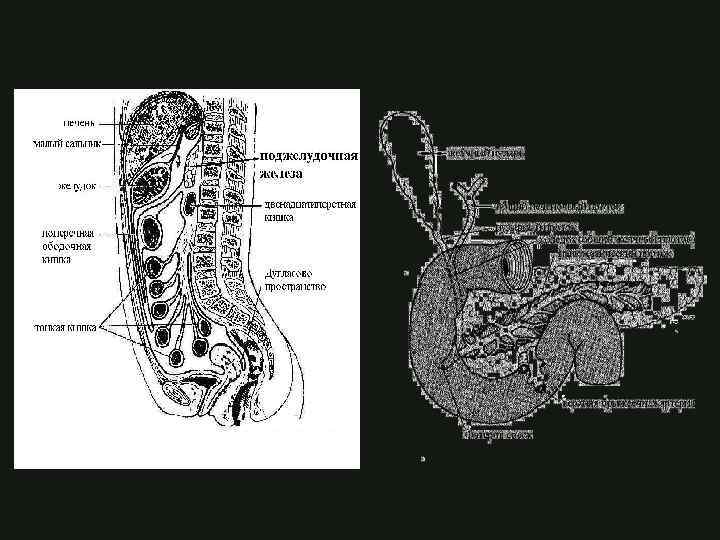

ЭМБРИОЛОГИЯ формируется на 4 неделе гестации из печёночного отростка вентральный зачаток формирует часть головки поджелудочной железы, крючковидный отросток и Вирсунгов проток КАФЕДРА ХИРУРГИИ МОСКОВСКОГО ФАКУЛЬТЕТА

ЭМБРИОЛОГИЯ формируется на 4 неделе гестации из печёночного отростка вентральный зачаток формирует часть головки поджелудочной железы, крючковидный отросток и Вирсунгов проток КАФЕДРА ХИРУРГИИ МОСКОВСКОГО ФАКУЛЬТЕТА

ЭМБРИОЛОГИЯ дорсальный зачаток формирует тело, хвост, часть головки поджелудочной железы и Санториниев проток на 37 день гестации формируется единый орган КАФЕДРА ХИРУРГИИ МОСКОВСКОГО ФАКУЛЬТЕТА

ЭМБРИОЛОГИЯ дорсальный зачаток формирует тело, хвост, часть головки поджелудочной железы и Санториниев проток на 37 день гестации формируется единый орган КАФЕДРА ХИРУРГИИ МОСКОВСКОГО ФАКУЛЬТЕТА